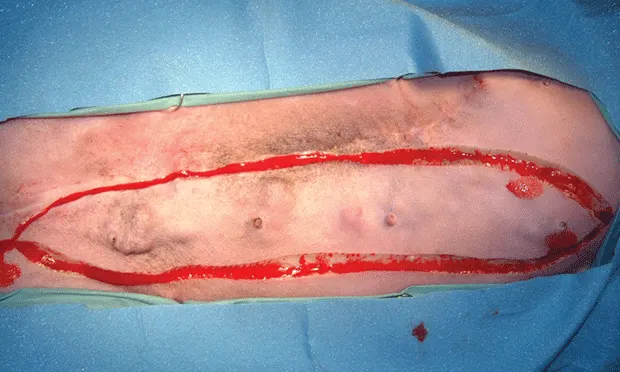

Unilateral mastectomy involves removal of all mammary tissue on one side of the midline (Figure 4). Mammary tissue extends from midline to the nipple line and is an equal distance lateral to the nipple line.

An elliptical incision should be made from the most cranial nipple to the most caudal nipple so that the medial extent of the ellipse is at midline and the lateral extent of the incision is equidistant on the lateral side of the nipple line (Figure 5).

All skin, mammary tissue, and fat down to the rectus fascia should be removed. The rectus fascia and underlying muscle should not be removed.